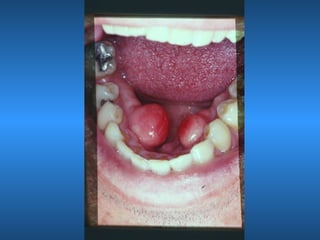

Torus

• Mandibular

• Paltino

• Etiologia